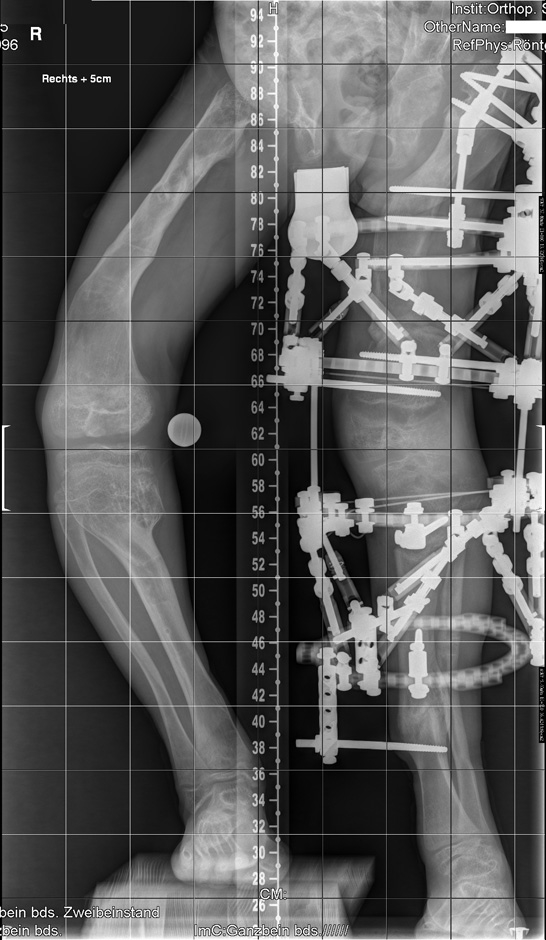

Figure 1

AP-view weight bearing X-ray of the patient before starting correction showed, at the pelvis and the femora, severe dysplasia of the capital femoral epiphyses, the acetabulae and the hypoplastic pelvis associated with bowing of the upper femoral shaft and Erlenmeyer flask appearance of the lower femora. Note the windswept deformity which presents abnormal valgus deformity in one knee in association with varus deformity in the other. The inferior femoral and superior tibial epiphyses look enlarged and severely distorted.